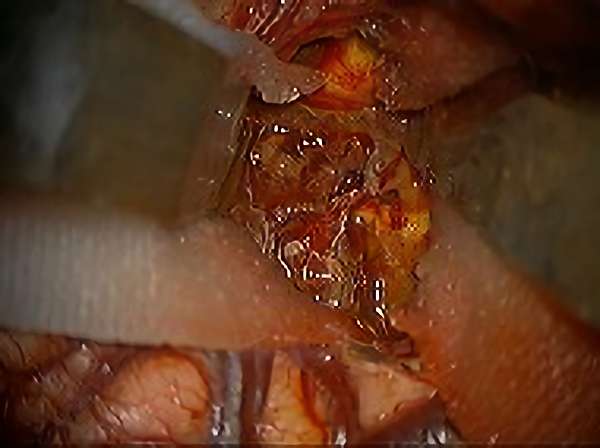

No.359 モニタリング

No.359 手術前

No.359 手術中

No.359 手術後

出血既往があり。2回の手術前血管内手術の後に、

Lateral transpeduncular approachにより再々出血予防を目的に

摘出手術を行う。完全摘出であることを確認した。

手術による合併症や後遺症なしで退院した。経過良好。